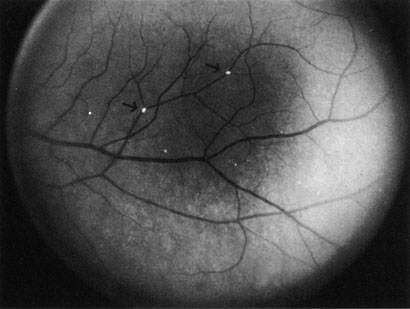

When a branch retinal artery is obstructed, there is usually whitening of the retina in the area supplied by the artery (Fig. 2). In most eyes (62% in one series), emboli are responsible for the obstruction.94 The temporal branch arteries are involved in almost all cases that have been reported,92,94 but whether this is because nasal branch retinal artery obstructions are rare or because such obstructions are simply asymptomatic is unknown. The characteristics of a branch retinal artery obstruction on intravenous fluorescein angiography are similar to those for central retinal artery obstruction.

Fig. 2. Multiple branch retinal artery obstructions in a young woman with encephalopathy and hearing loss. (Photograph courtesy of Jack W. Pierce, M.D.)

Occasionally, patients present with a bilateral branch retinal artery obstruction.94 Some have obstructive retinal arteries without evidence of systemic abnormalities,95,96 whereas others have accompanying symptoms such as deafness.97,98 Some younger patients—usually women—have been reported to have an idiopathic syndrome of branch retinal artery obstruction, encephalopathy, and hearing loss (Susac syndrome).99–104,406 The eyes on these patients are characterized by significant systemic thromboembolic events; recurrent bilateral retinal arterial occlusions; segmental arteriolar staining by fluorescein angiography, occasionally associated with periarteriolar retinal whitening or mild vitreous cells; and a predilection for vestibuloauditory or transient sensorimotor symptoms.104 Some patients, however, present with only recurrent bilateral retinal arteriolar occlusions and never develop the associated vestibuloauditory or sensorimotor systems; whether these patients have a partial manifestation of Susac syndrome is unknown. The etiology of branch retinal artery obstruction in most cases is similar to that of central retinal artery obstruction (see Table 1). Retinal diseases (such as toxoplasmosis) can also cause branch retinal artery obstruction.